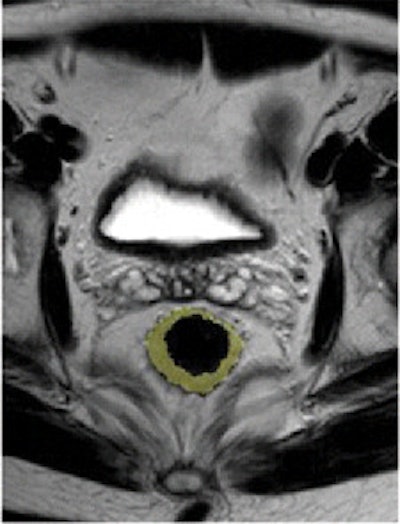

Pre- and post-treatment MRI was performed with a 1.5-tesla system (Intera R10, Philips Healthcare) using an eight-element pelvic phased-array surface coil. The subjects were imaged in the prone position after the placement of a thin rectal catheter in the rectum.

After initial localization imaging, researchers acquired MR images of the pelvis and rectum, with T2-weighted images obtained in the transverse, coronal, and sagittal planes during the scanning time of approximately 30 minutes.

Two radiologists, who were blinded to clinical information about each patient, independently evaluated the images obtained before and after chemotherapy and radiation treatment.

The MR images calculated the mean tumor volume was 58 cm3 ± 75 before chemotherapy/radiation treatment and 20 cm3 ± 31 after therapy. The mean tumor volume reduction ratio in all patients was 68% ± 23.

Researchers also found tumor volume reduction rates after chemotherapy/radiation treatment were significantly different between patients with TRG 1 or 2 and subjects with TRG 3 or 4. "The mean tumor volume reduction was 57 cm3 ± 20 in patients with TRG 1 or 2 and 83 cm3 ± 18 in individuals with TRG 3 or 4 (P < .0001)," they wrote, adding there were no significant differences seen according to the location of the tumor.